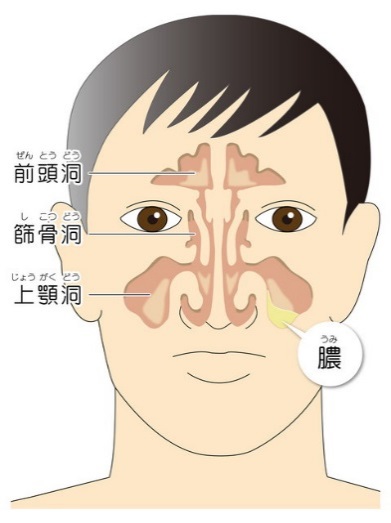

副鼻腔というのは、目の上にある前頭洞(ぜんとうどう)、目と鼻の間にある篩骨洞(しこつどう)、鼻の奥にある蝶形骨洞(ちょうけいこつどう)、頬の奥にある上顎洞(じょうがくどう)からなり、これは全てつながっています。この副鼻腔に炎症が起こり、副鼻腔内に膿が溜まって副鼻腔炎が発症します。

副鼻腔というのは、目の上にある前頭洞(ぜんとうどう)、目と鼻の間にある篩骨洞(しこつどう)、鼻の奥にある蝶形骨洞(ちょうけいこつどう)、頬の奥にある上顎洞(じょうがくどう)からなり、これは全てつながっています。この副鼻腔に炎症が起こり、副鼻腔内に膿が溜まって副鼻腔炎が発症します。